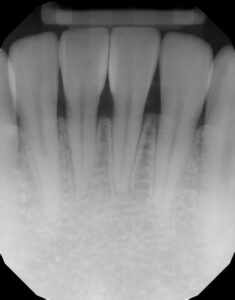

Final shaping was completed with the 3M® Soflex Coarse disc, followed by a final polish using Bioclear Magic Mix pre-polishing paste and the Bioclear Rockstar Polishing cup. (Figure 7) Rubber dam was removed, and the smile was evaluated for facial harmony. Adjustments were not needed for this patient as she was pleased with all aspects of her smile. (Figures 8-9) Post operative radiographs were taken to assess for excess composite and quality of technique and can be compared to the pre-operative x-rays. Post operative radiographs are useful for quality control. Notice how a smooth “infinity edge” can be created with the Bioclear matrices and technique. This is essential for a healthy tissue response. (Figures 10-11).

The matrix is removed from tooth #25, (Fig 24) and then #24 is injection molded. This to ensure a snug contact. The teeth are then rapidly sculpted together for sake of symmetry and efficiency. The final step is the Rock Star Polish. Invisible infinity edge margins are placed at mid-tooth. (Figs 25, 26) At one-year recall, the treated area is essentially bacteria and calculus-free, and the neighboring untreated embrasure is filled with calculus. The obvious health and quality of life of the treatment are a bonus to the esthetic benefits. (Fig 27) Pre- and post-operative radiographs demonstrate the imperceptible interface of composite to tooth and the void -free quality of the composite which is the goal if injection over-molded heated monolithic composite. (Figs 28, 29)